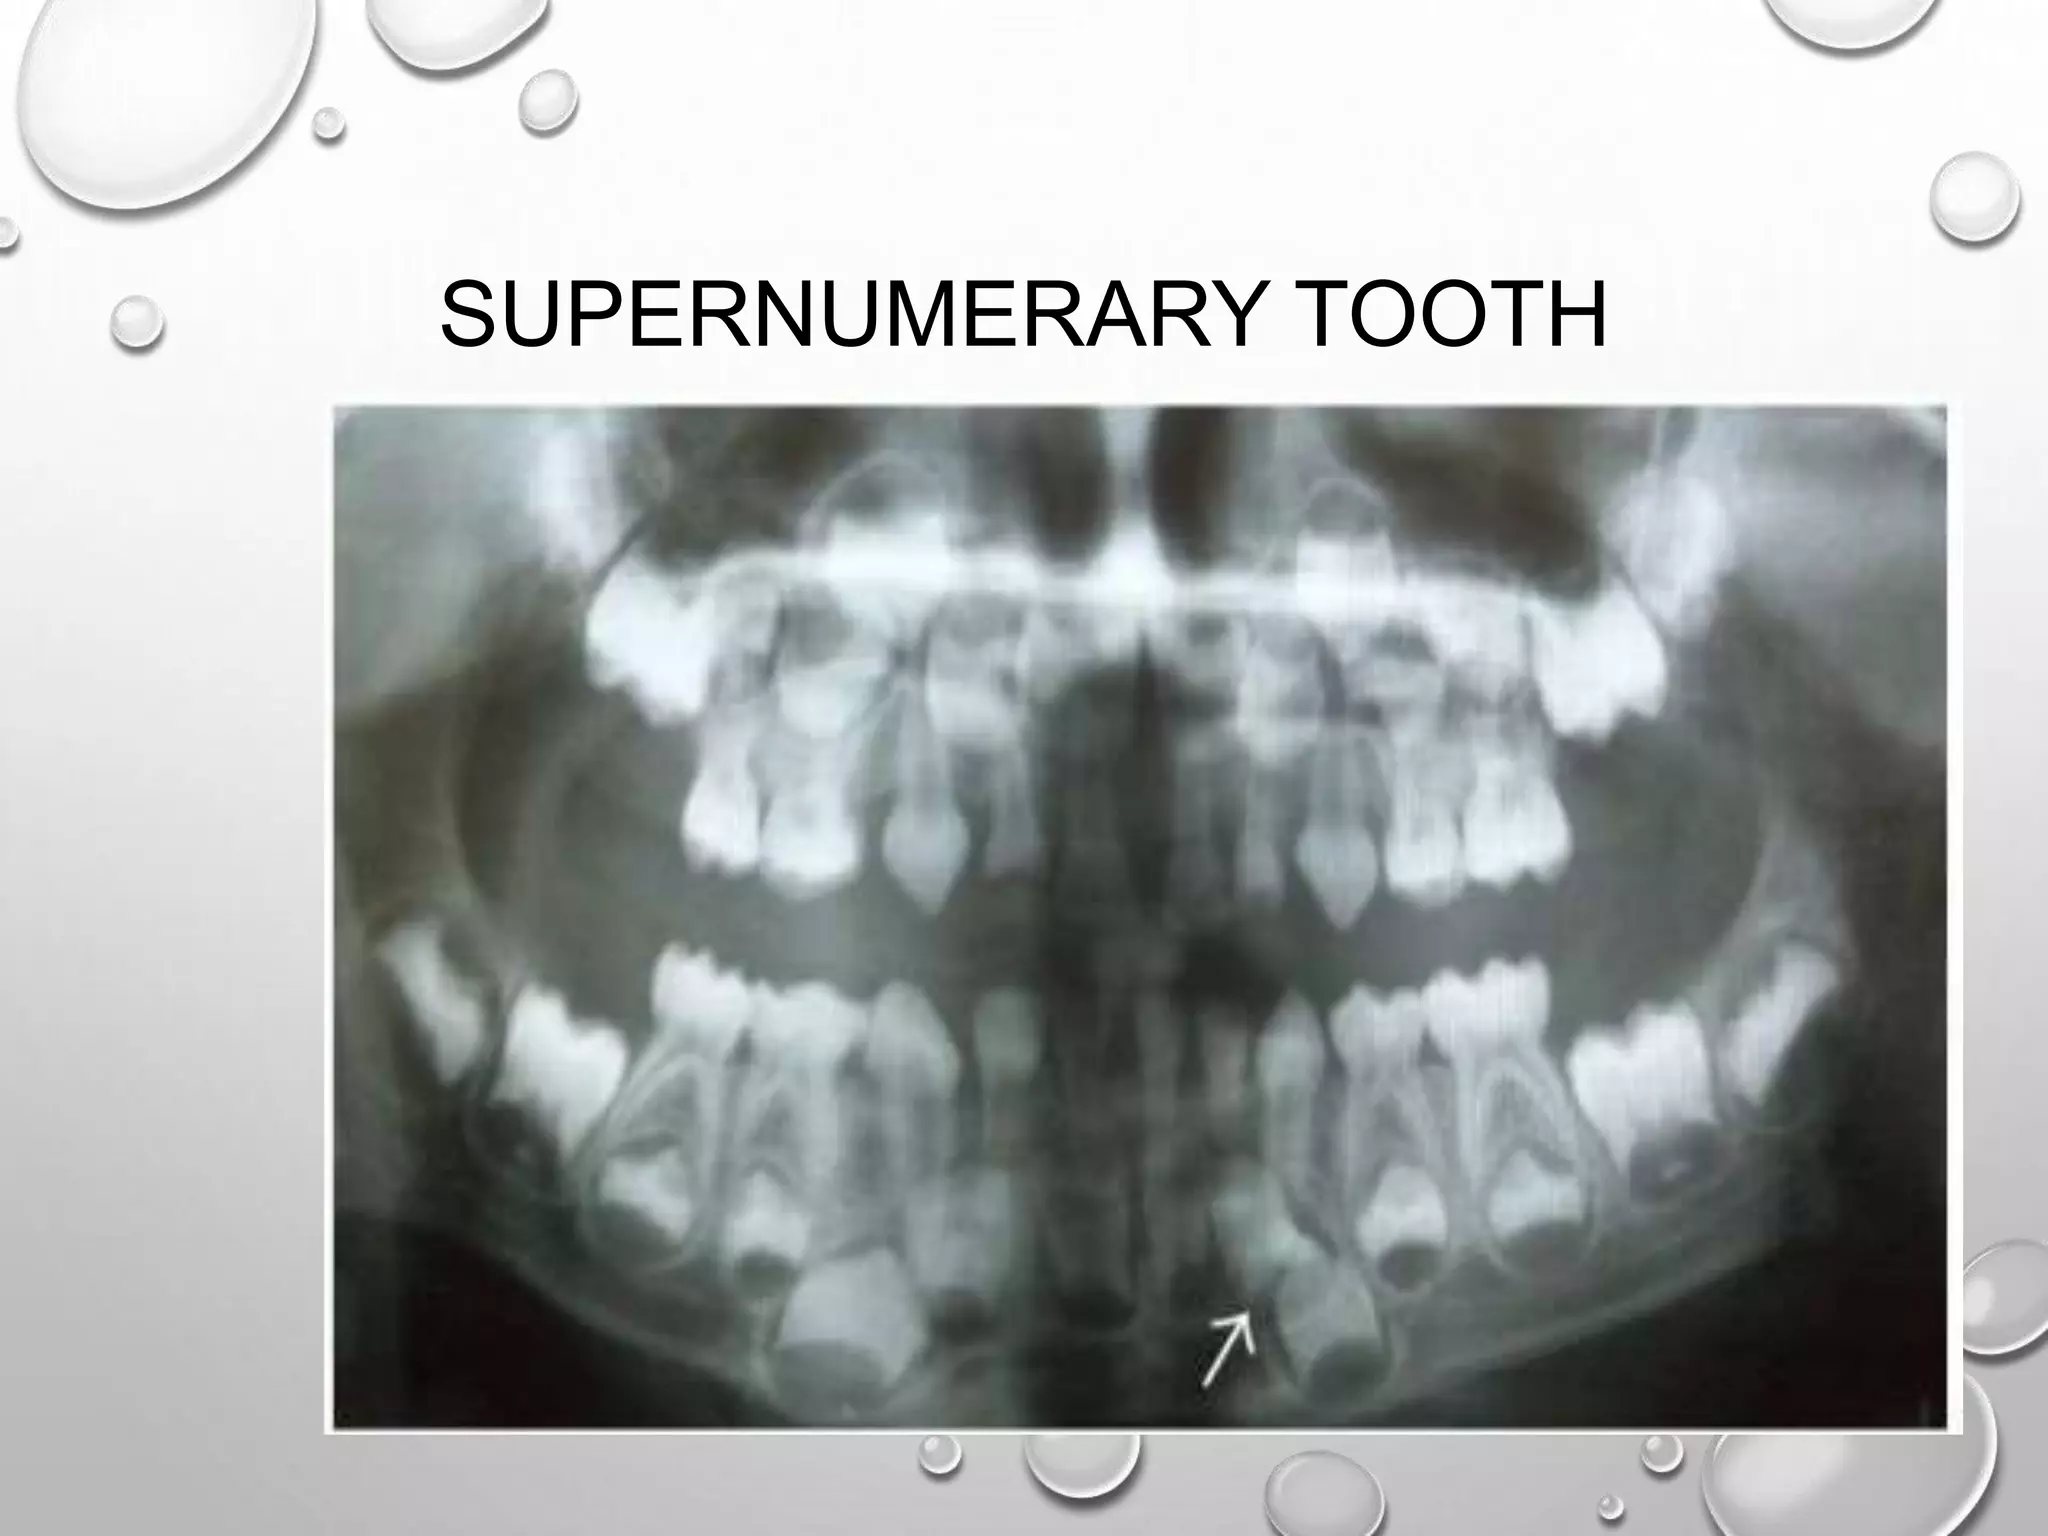

SUPERNUMERARY TOOTH

MESIODENS